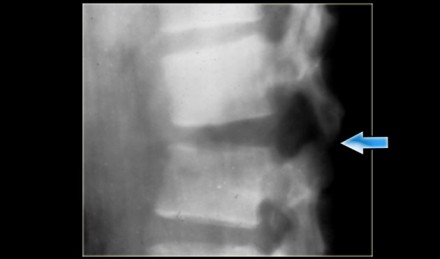

The sagittal reconstructions of the CT demonstrate that the posterior part of the vertebral body is of normal height, but there is some involvement of the posterior part of the vertebral body.

On the left a coronal reconstruction and an axial image at the level of the fracture.